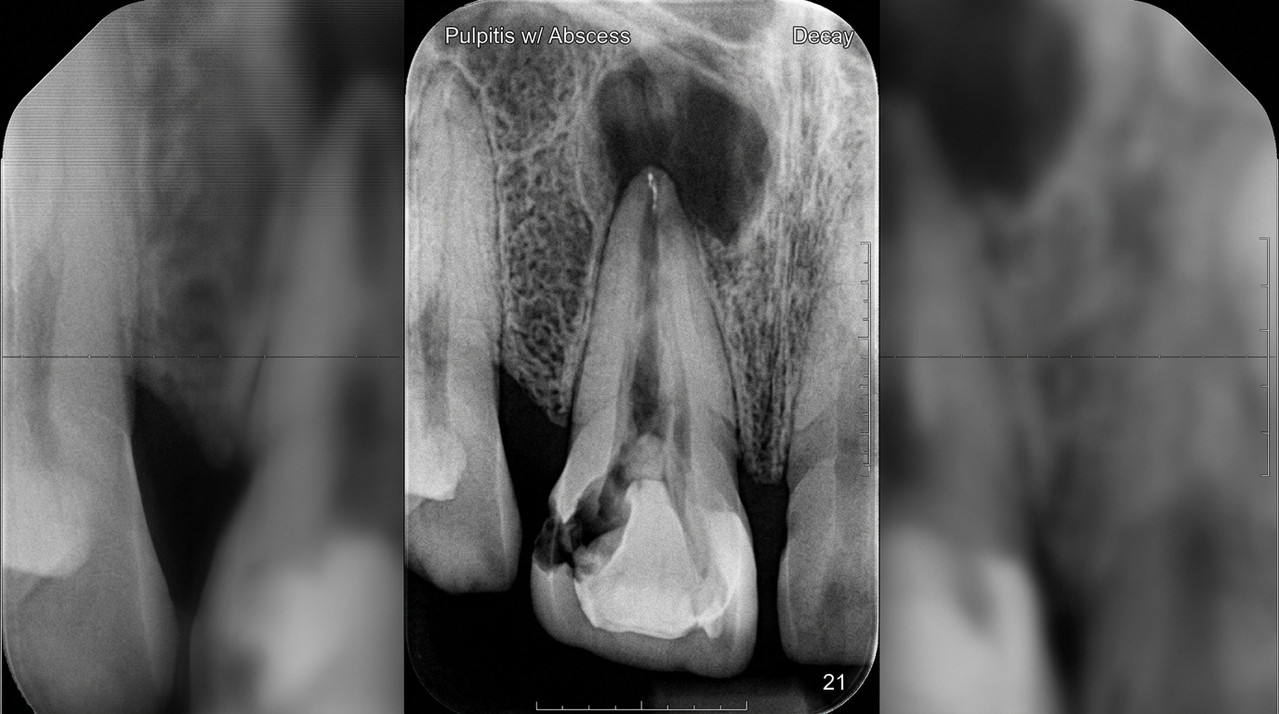

Переход к пульпиту происходит, когда бактерии достигают нервов. Пульпит — воспаление внутренней ткани зуба — вызывает пульсирующую боль, не купируемую анальгетиками вроде Кеторола. В 2026 году в России пульпит диагностируют у 40% пациентов с кариесом, по данным Минздрава. Лечение требует удаления нерва и пломбирования каналов, что дороже и сложнее профилактики.

Рентген зуба с глубоким кариесом: видны изменения в пульпе и корне.

Далее следует периодонтит — воспаление тканей вокруг корня. Это уже системная проблема: инфекция выходит за зуб, вызывая отек десны и подвижность зуба. В тяжелых случаях формируется гранулема или киста, видимые на рентгене. Российские стандарты лечения по приказу № 910н предусматривают эндодонтию или удаление. Игнорирование приводит к потере зуба в 70% случаев.